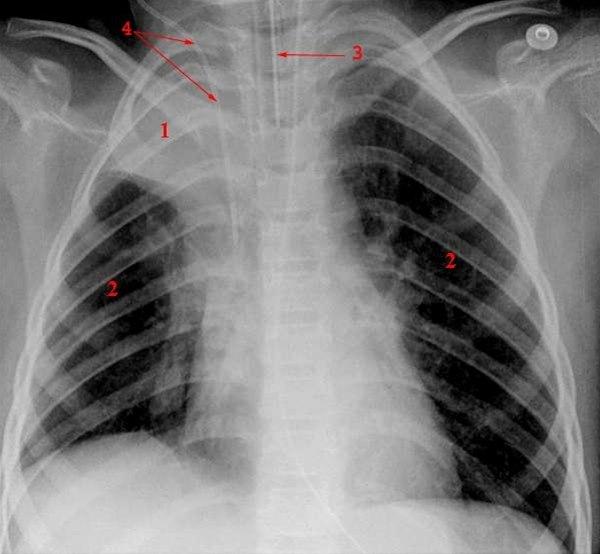

Lunger med atelektaseTypiske plager er tungpusthet og hoste. Når dette opptrer like etter eller under en lungebetennelse, eller i forbindelse med operasjoner, vil man ofte få mistanke om tilstanden. Men sikker diagnose stilles først ved røntgenundersøkelse av lungene.

Ved røntgen av lunger er de typiske forandringene at atelektasen viser seg som en liten kileformet ensartet skygge på røntgenbildet